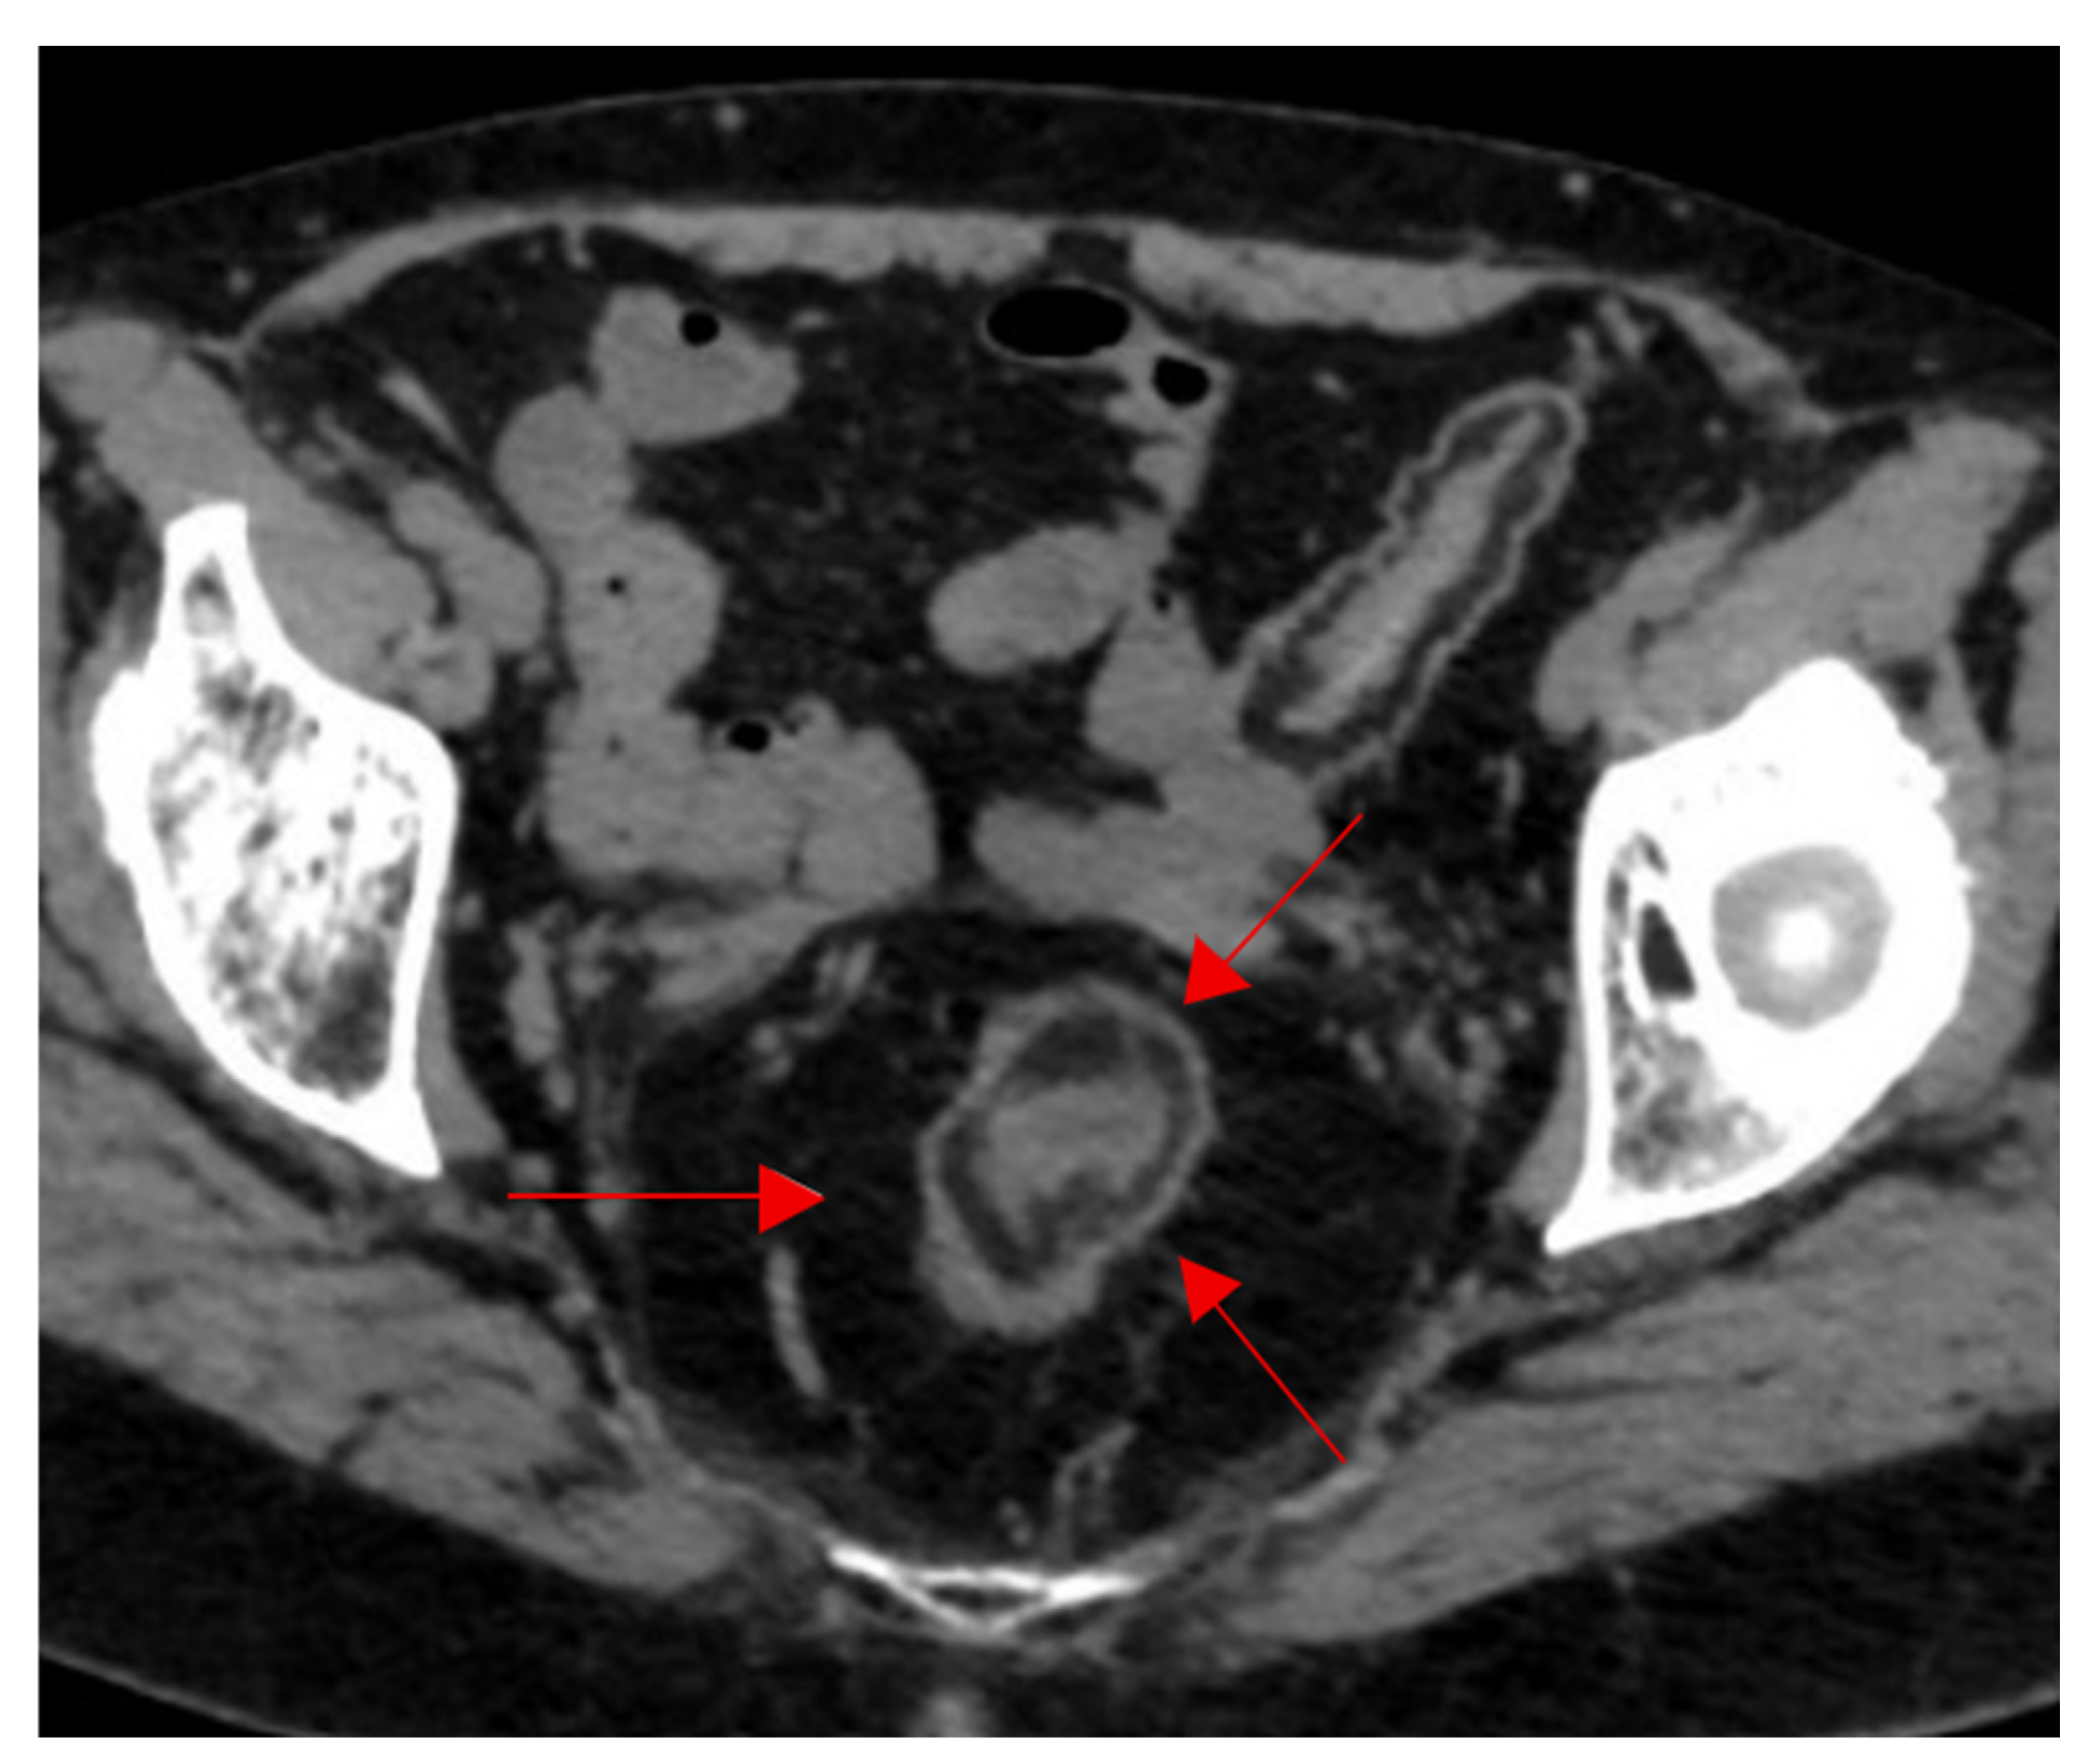

Abdomen and Pelvis

- Dalrymple, N.; Casford, B.; Raiken, D.; Elsass, K.; Pagan, R. Pearls and Pitfalls in the Diagnosis of Ureterolithiasis with Unenhanced Helical CT. Radiographics 2000, 20, 439–447. [Google Scholar] [CrossRef] [PubMed]

- Guest, A.; Cohan, R.; Korobkin, M.; Platt, J.; Bundschu, C.; Francis, I.; Gebramarium, A.; Murray, U. Assessment of the Clinical Utility of the Rim and Comet-Tail Signs in Differentiating Ureteral Stones from Phleboliths. AJR Am. J. Roentgenol. 2000, 177, 1285–1291. [Google Scholar] [CrossRef]

- Luk, A.C.; Cleaveland, P.; Olson, L.; Neilson, D.; Srirangam, S. Pelvic Phlebolith: A Trivial Pursuit for the Urologist? J. Endourol. 2017, 31, 342–347. [Google Scholar] [CrossRef]